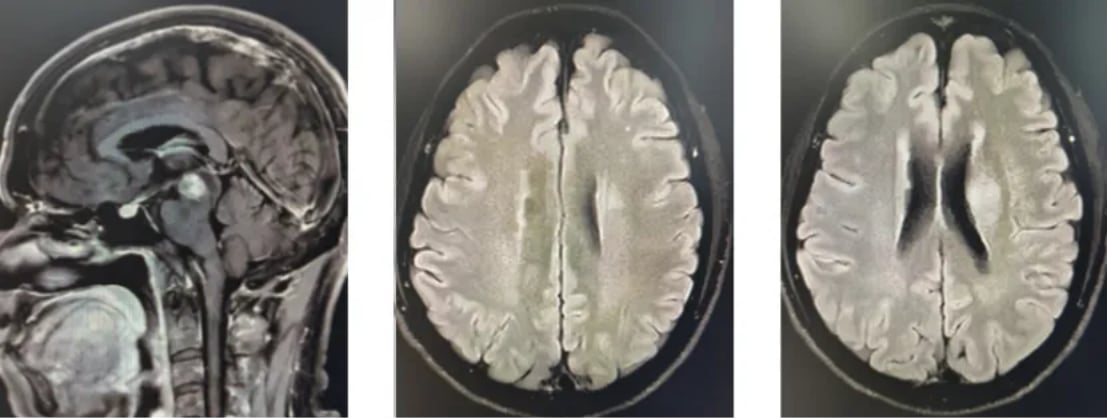

不幸的是,在2024年5月的复查中,MR影像提示部分病灶范围较前增大,表明肿瘤出现进展。面对疾病进展,医疗团队迅速调整策略,为患者制定了再程放化疗方案。此次治疗在放疗的基础上,联合使用了替尼泊苷和替莫唑胺(Temozolomide)两种化疗药物。经过新一轮的同步治疗和后续的维持化疗,患者的病情再次得到有效控制。最近的MR复查结果令人鼓舞,显示病灶范围较前缩小,疗效评价为部分缓解(PR)。

图4 二线治疗后影像学